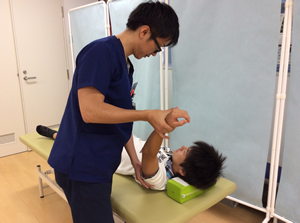

リハビリテーション

反復性肩関節脱臼などは、肩関節以外にも肩甲骨などの他の部位の柔軟性が重要となります。手術直後は肩関節以外の治療が中心となります。また患者さんによっては痛みのない範囲で理学療法士が手術した肩を動かす場合があります。

手術後3週目のリハビリの様子です。

肩関節の柔軟性向上を図っていきます。

手術後3ヶ月頃のリハビリの様子です。

体幹や肩甲骨周囲のトレーニングを積極的に行ないます。

手術後5ヶ月頃のリハビリの様子です。

スポーツ復帰に向けて,さらにトレーニングの強度を上げていきます。